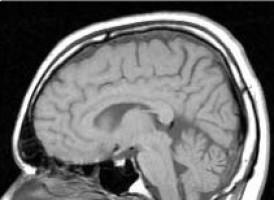

Researchers at the University of Central Lancashire (UCLan) believe they have found a way to cut the time it takes to diagnose brain tumours.

Dr Baker found molecular differences when infrared light was transmitted directly at gliomas - an aggressive type of brain tumour.

The light detected molecular vibration from the blood serum, which it is hoped will eventually be used to identify different disease states i.e. cancer or non-cancer.